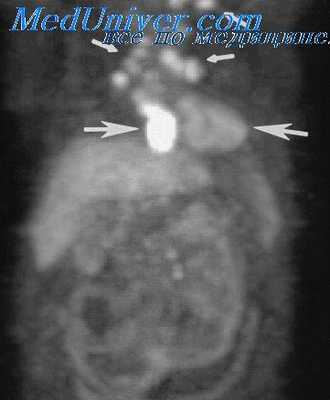

КТ ОГК. Массивное объемное образование верхнего средостения с объемным воздействием на трахею, исходящее из щитовидной железы.